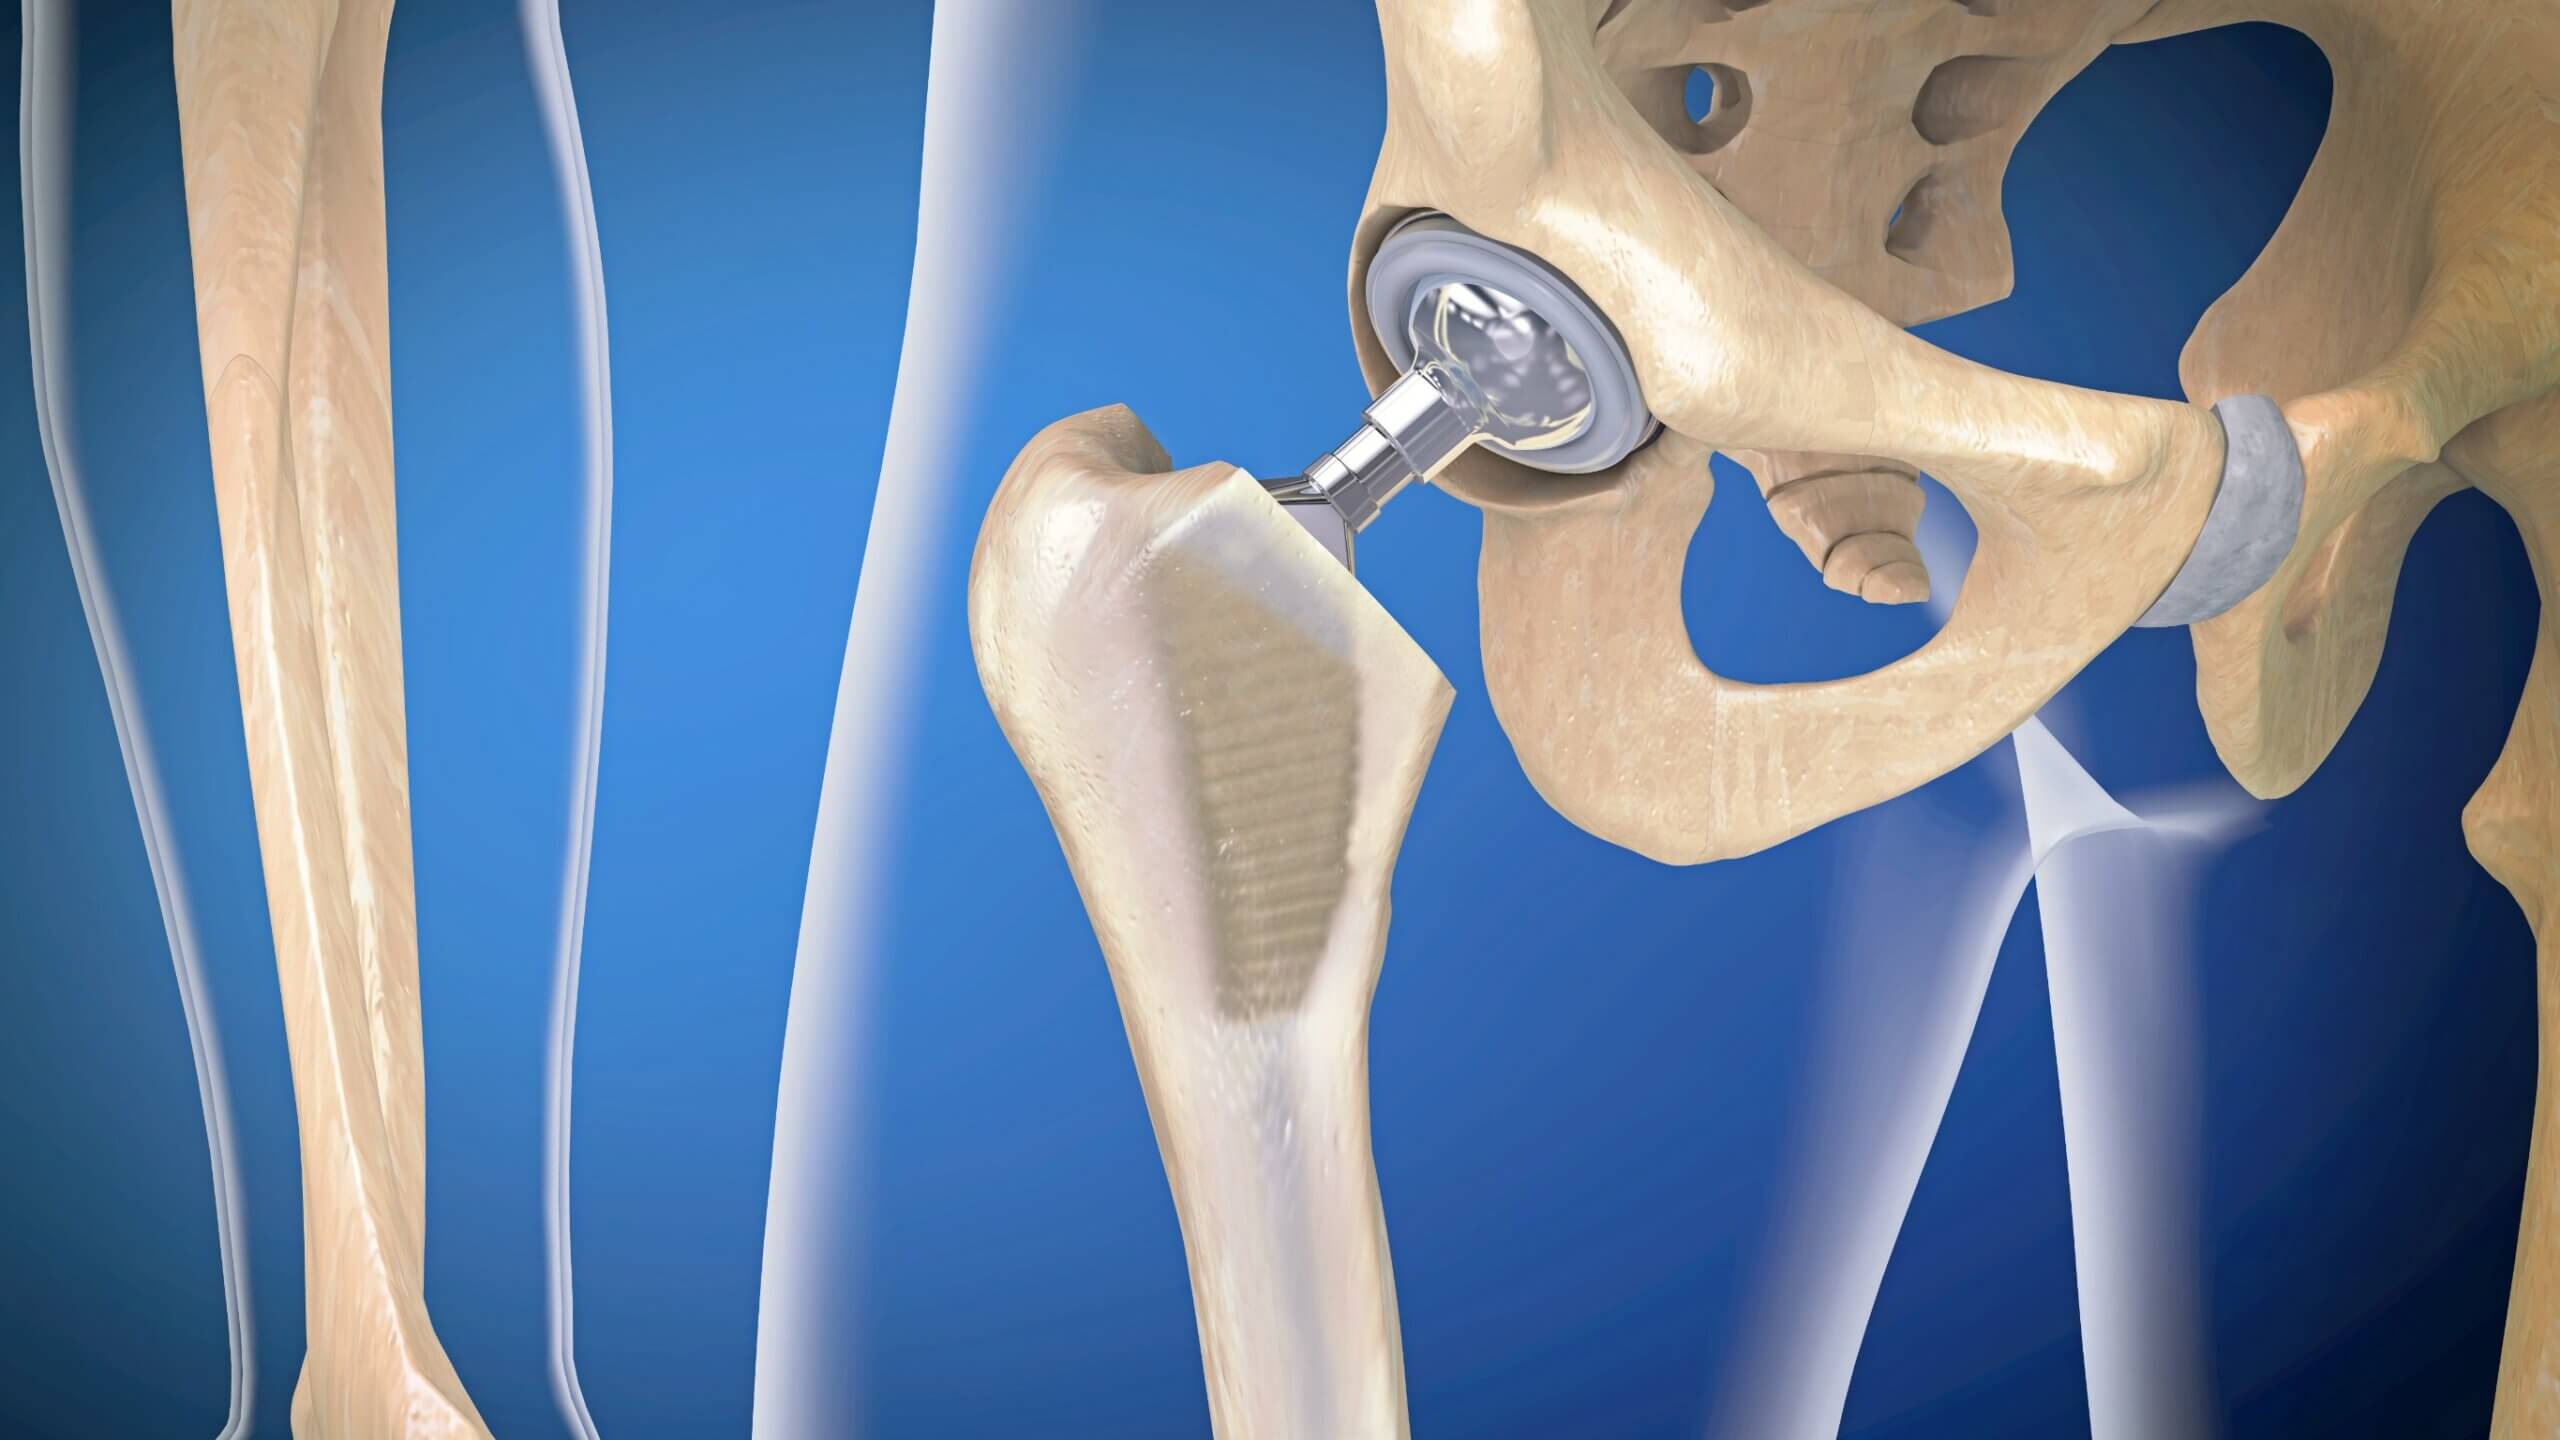

Замена таз сустава

Замена таз сустава 113 фотографий